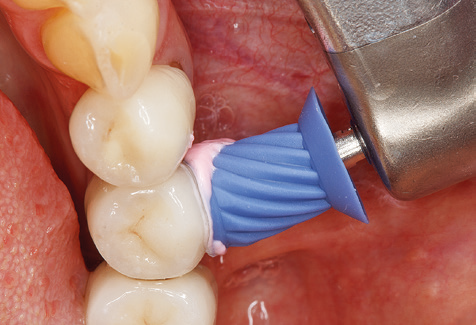

Following machine cleaning of the tooth and implant surfaces, the surfaces of the natural teeth are cleaned manually using standard hand instruments. When performing manual cleaning, particular attention must be given to maintaining the correct angle of application, appropriate sharpness, good support and working with the curette from apical to coronal. Either titanium or carbon curettes should be used for post-cleaning of the implant structures (Fig. 8). In addition to the use of ultrasonic devices, power jet devices can also be used in conservative dentistry. However, it must be taken into consideration that these procedures are not suitable for removing hard deposits and thus they cannot replace the use of hand instruments and ultrasonic instruments completely. In all cases, cleaning is followed by mechanical polishing of the accessible tooth and implant surfaces with polishing cups and polishing compounds (Fig. 9).

Fig. 9: The accessible implant and tooth surfaces are polished with polishing cups and suitable polishing compounds. – Fig. 10: Repeat instruction in the use of appropriate aids for oral hygiene at home should also form part of SPT. – Fig. 11a and b: Clinical situation 12 years after insertion of the prosthetic restoration. During this period, only a veneering ceramic fracture on tooth 47 and the requirement for endodontic treatment of tooth 12 were observed. All restorations are still functioning as intended.

Fig. 4: Flexible probes with millimetre markings are recommended for the probing of dental implants (e.g. Colorvue Kit PCV11KIT6, Hu­Friedy). – Fig. 5a and b: A straight working tip (1P, W&H Dentalwerk Bürmoos GmbH) is a suitable instrument for use on all natural teeth. – Fig. 6: Curved working tips (3Pr/3Pl, W&H Dentalwerk Bürmoos GmbH) lend themselves to the processing of difficult-to-reach areas of the tooth and root surfaces (e.g. furcations). – Fig. 7: The tapered, hexagonal implant cleaning tip (1I, W&H Dentalwerk Bürmoos GmbH) permits atraumatic and efficient cleaning of the crown and abutment surfaces. – Fig. 8: Titanium and carbon curettes are suitable instruments for the manual cleaning of the implant surfaces.